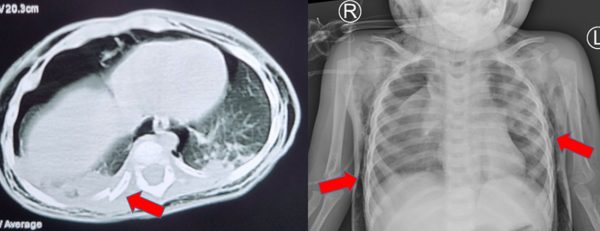

Tại đây ghi nhận: trẻ đừ, môi tím, khó thở, SpO2 85% được đặt nội khí quản, thở máy, chụp CT scan đầu ngực bụng ghi nhận: tràn khí dưới da vùng bụng, hông, lưng, ngực, cổ 2 bên, xẹp thùy trên phổi 2 bên và thùy giữa phổi (P). Mất liên tục thành khí quản cạnh gốc carina bên (P), theo dõi vỡ khí quản, tràn khí trung thất – gãy xương sườn 8, 9, 10. Không thấy khối choán chỗ trong hộp sọ.

Trẻ được chuyển bệnh viện Nhi Đồng Thành Phố. Tại đây, trẻ được hội chẩn các chuyên khoa hô hấp, tai mũi họng, hồi sức ngoại, gây mê hồi sức chẩn đoán: Vỡ khí quản – Gãy xương sườn 8,9,10 (P), thống nhất xử trí mở ngực phẫu thuật tạo hình khí quản, nội soi phế quản kết hợp khi mổ.